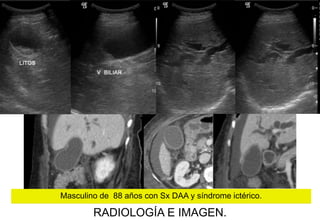

Masculino de 88 años con Sx DAA y síndrome ictérico.